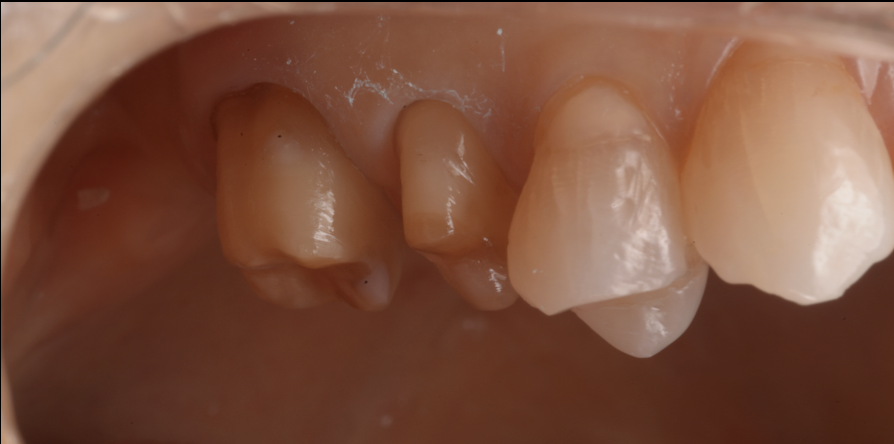

治療前後比較

治療前

治療後